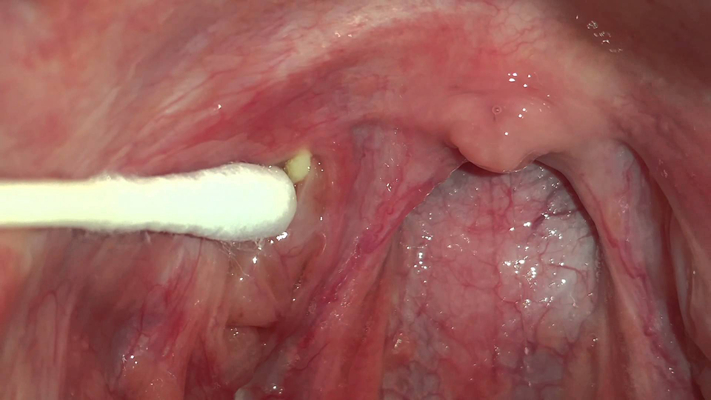

扁桃體結石

扁桃體結石

扁桃體結石

扁桃體結石

扁桃體結石

扁桃體結石

扁桃體結石

扁桃體結石

扁桃體結石

扁桃體結石

扁桃體結石

扁桃體結石

扁桃體結石

扁桃體結石

扁桃體結石

扁桃體結石

扁桃體結石

扁桃體結石

扁桃體結石

扁桃體結石